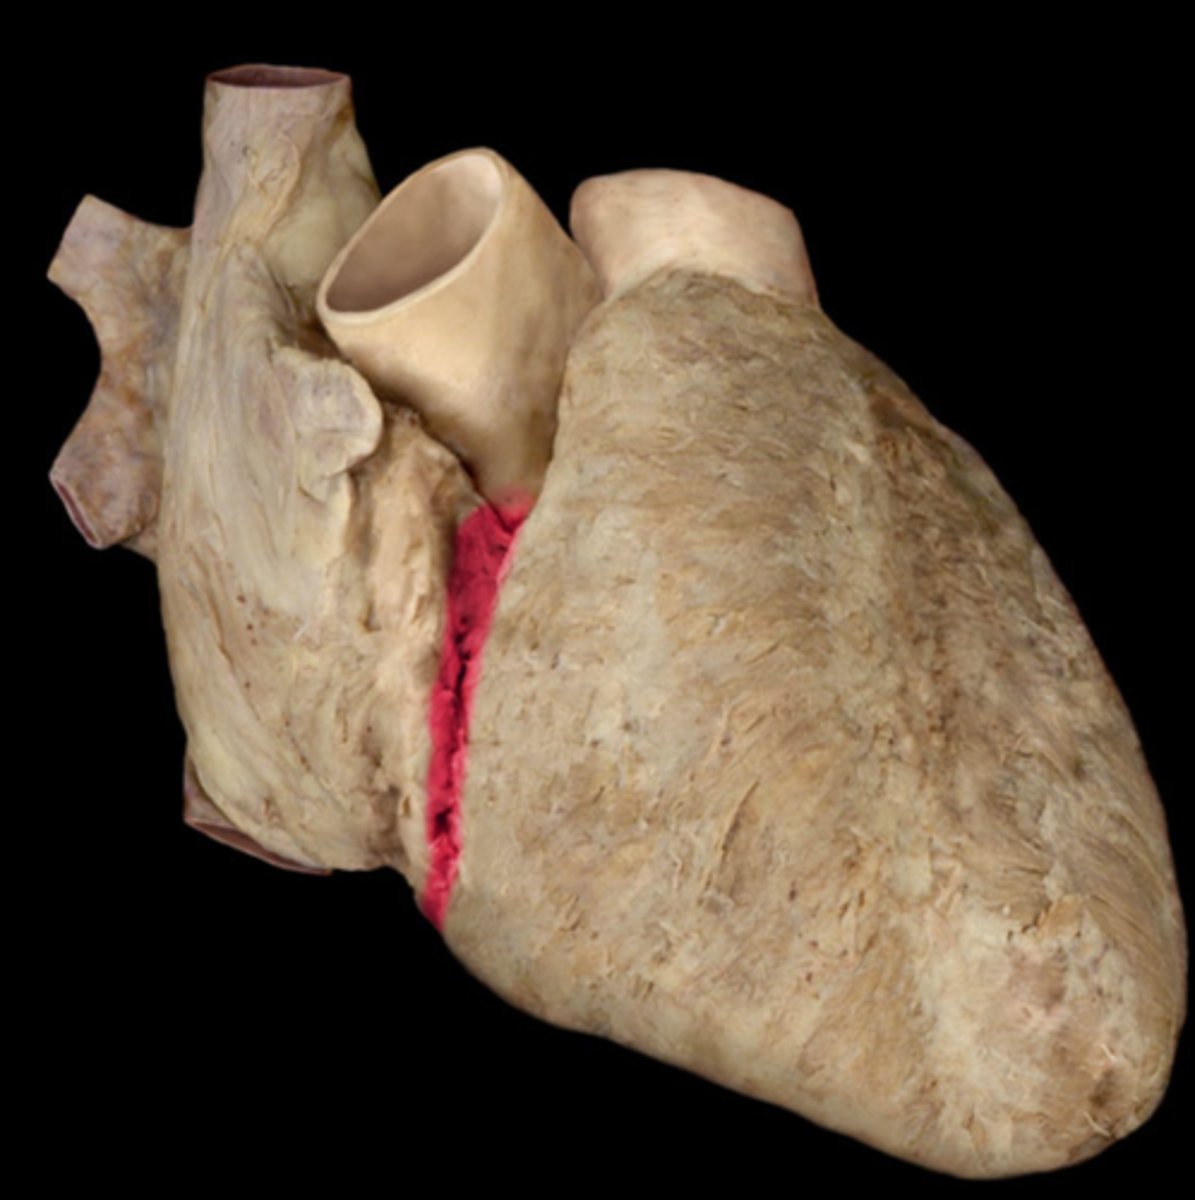

Coronary sulcus

Depression, on top of the heart, inside.

anterior interventricular sulcus

depression. anterior of the heart.

ligamentum arteriosum

feature. Has blood clot, also right next to black color.